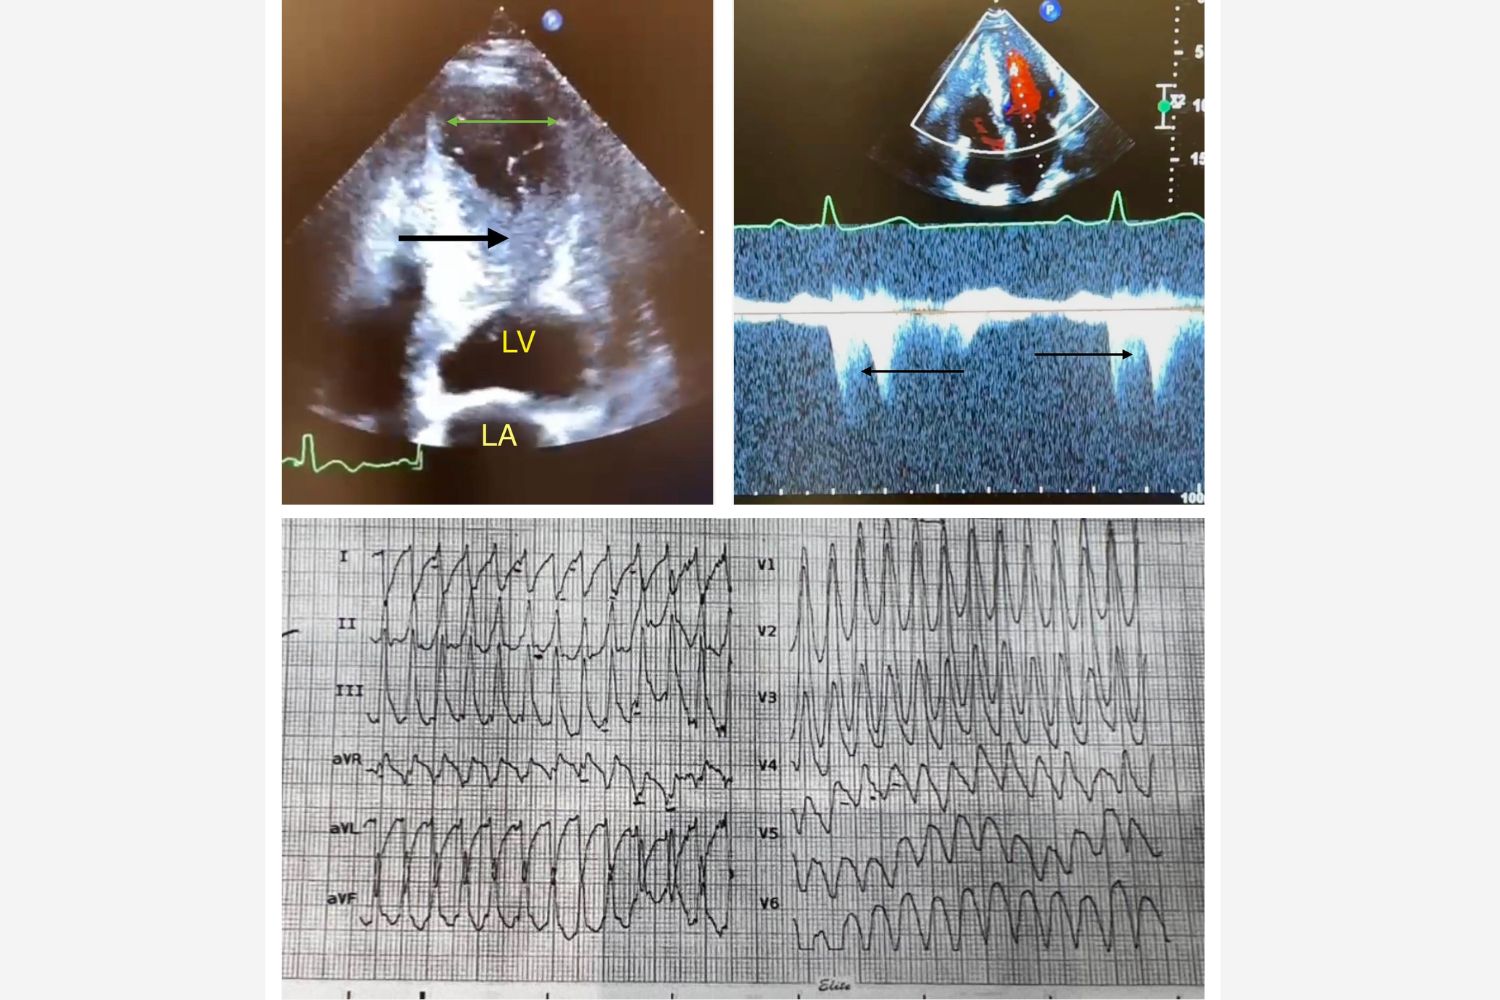

Image of the Week - 19 November 2025

Image of the week